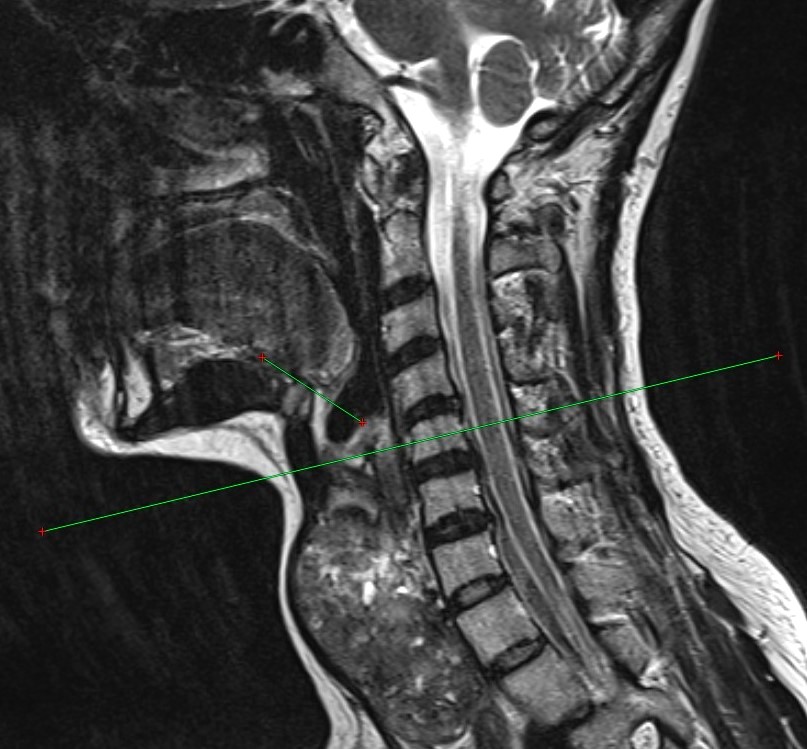

Хирургическое лечение остается основным методом борьбы с заболеваниями щитовидной железы. Существующие техники перевязки верхних полюсов ориентированы на нормальный объем органа и не учитывают анатомические изменения при его увеличении.

Новый метод позволяет точнее определять толщину и уровень расположения верхнего полюса увеличенной железы, а также снизить риск интра- и послеоперационных осложнений, таких как кровотечение и повреждение верхнего гортанного нерва.

Фото: Центр медиакоммуникаций Оренбургского государственного медицинского университета